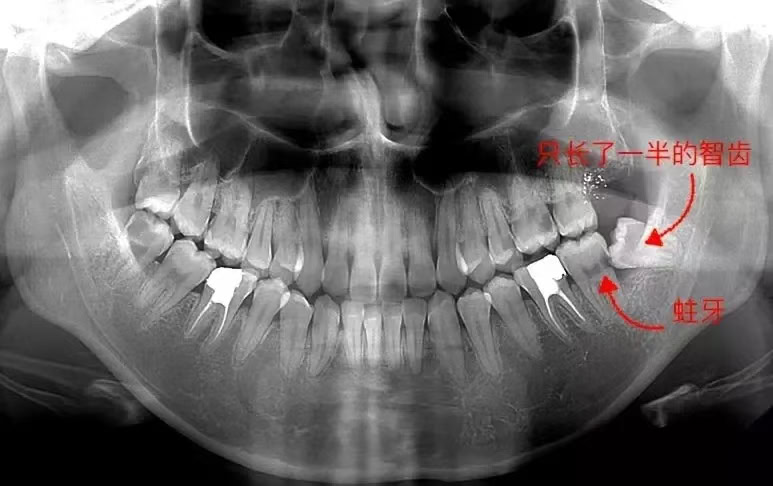

智齒同第二磨牙之間嘅狹窄空間容易積聚食物殘渣同細菌,形成盲袋,增加第二磨牙遠中(靠近智齒一側)面發生齲齒嘅風險。尤其當智齒只有一部分露出,更易藏污納垢。

3. 牙髓炎

第二磨牙若因智齒阻生而產生齲齒,可能會進一步發展成為牙髓炎,即牙齒內部嘅神經組織受感染,引致劇烈疼痛。